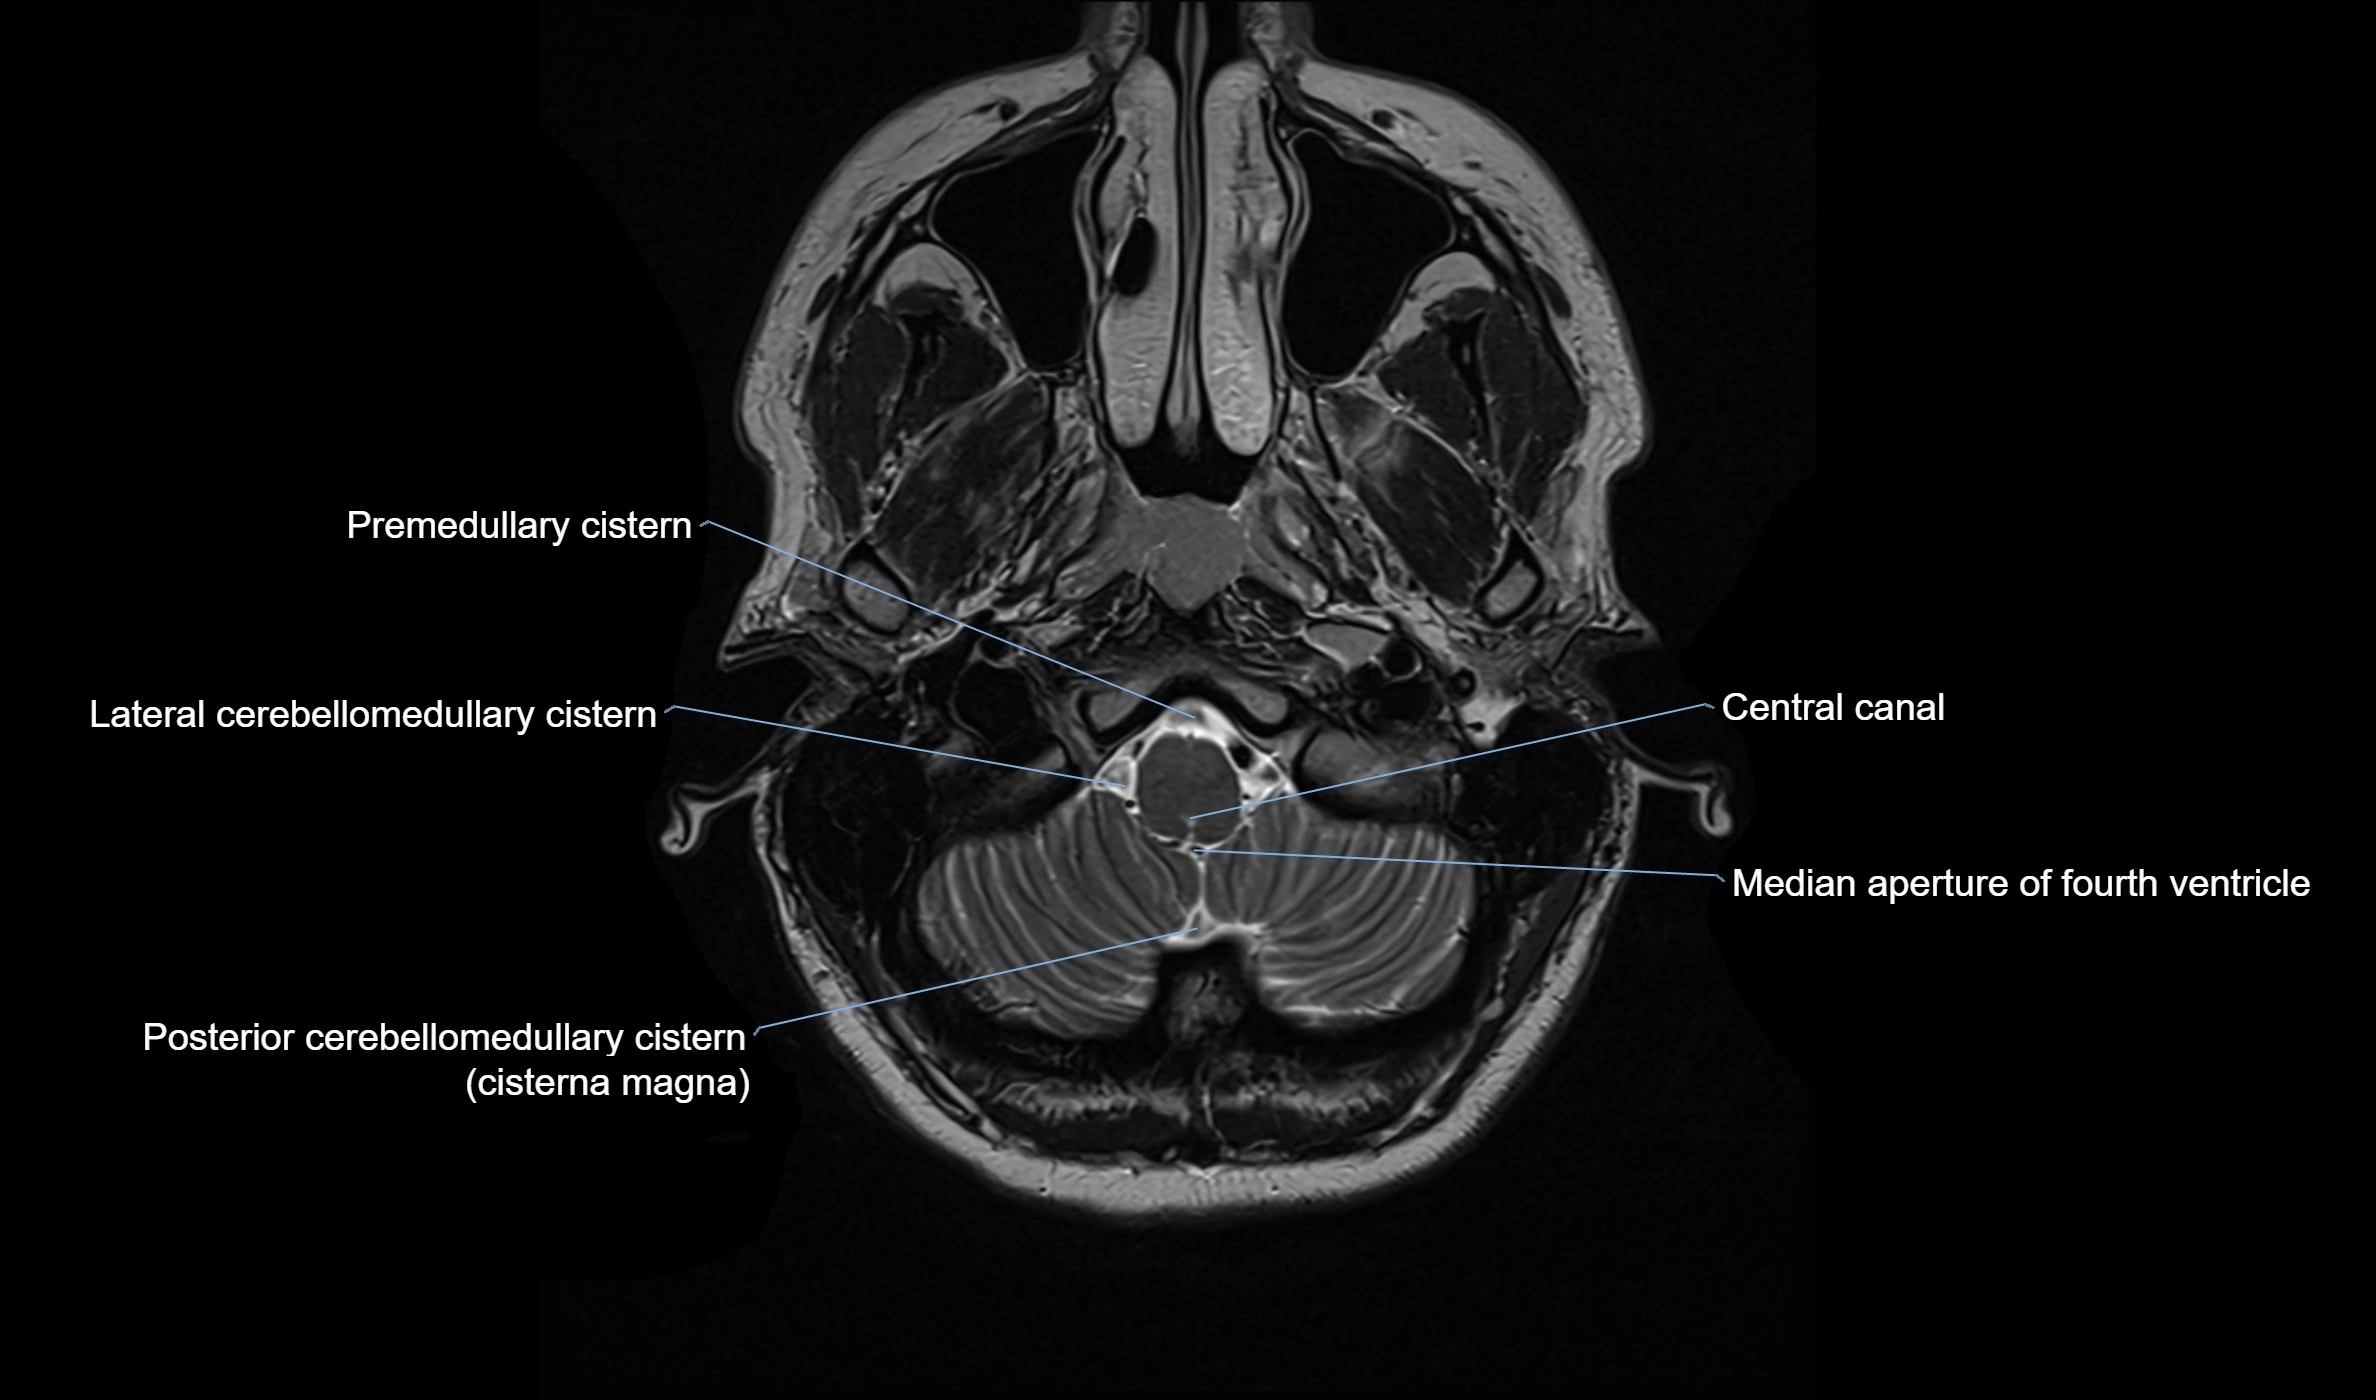

MRI images

image